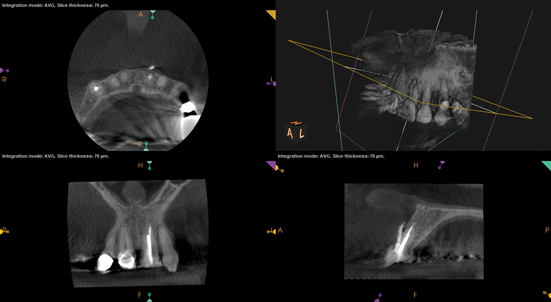

Other common risks associated with post placement include the occurrence of root fracture, perforation, and apical leakage as well as the development of caries (Figure 1 through Figure 3).9 How the post space is prepared significantly affects the ability of the root canal filling material to create a seal.11 Apical leakage increases in correlation with the amount of gutta percha removed from an endodontically treated tooth, increasing the risk of reinfection.11 The risks of fracture and perforation must also be seriously considered. After the performance of endodontic treatment alone, furcation-side dentin thickness in the distal roots of mandibular molars has been shown to be less than 1 mm in more than 80% of teeth.12 After preparation of the post space, the remaining dentin thickness in the buccal roots of premolars has been shown to be often less than 1 mm.13 The remaining thickness of the root dentin after endodontic and post placement procedures is the factor most highly correlated with future resistance against root fractures.13 These anatomic studies underscore the need for judicious preparation, and the risks of post placement underscore the need for careful case selection.

(1.) A radiograph of a root fracture associated with a threaded post, cone-beam computed tomography views of a perforation associated with a post, and a radiograph demonstrating evidence of apical leakage associated with posts, respectively.

Figure 1

(2.) A radiograph of a root fracture associated with a threaded post, cone-beam computed tomography views of a perforation associated with a post, and a radiograph demonstrating evidence of apical leakage associated with posts, respectively.

Figure 2